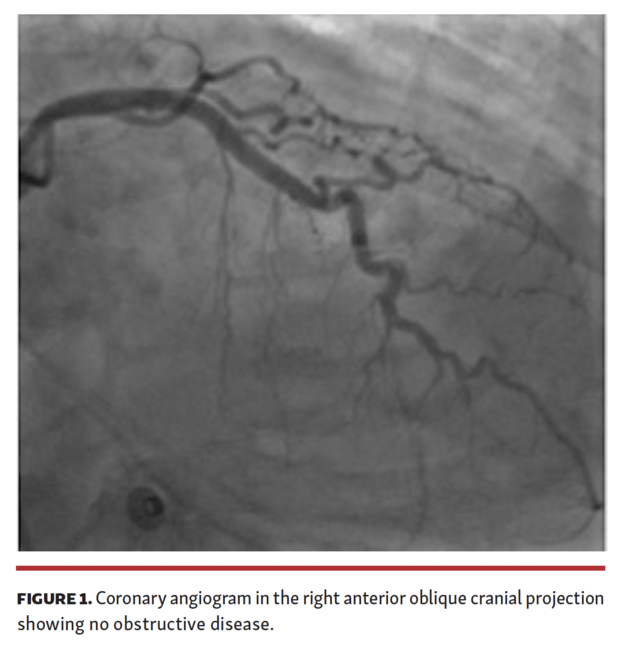

A 49-year-old female patient presented with progressive shortness of breath, and abdominal and leg swelling. Her medical history was significant for stage 3 breast cancer, which was treated with multiple rounds of chemotherapy and radiation over 7 years. Electrocardiogram showed Q-waves in V1 and V2. Bedside echocardiogram showed a left ventricular ejection fraction of 25% with severe global hypokinesis. Troponin I was elevated at 1.15 ng/mL. She was taken to the cardiac catheterization lab, where a coronary angiogram showed no obstructive coronary artery disease (Figure 1), but revealed an unusual motion abnormality of the coronary arteries that is typical for pericardial constriction (Videos 1 and 2). The pericardium was unremarkable on fluoroscopy. Subsequent echocardiography revealed other signs of constrictive pericarditis with thickened pericardium, interventricular interdependence, and annulus reversus (lateral e' velocity < medical e' velocity).